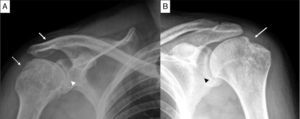

Anteroposterior projection of shoulders. (A) The view of right shoulder shows erosions in the greater tuberosity (dashed arrow), narrowing of the glenohumeral joint space (arrowhead) and ankylosis of the acromioclavicular joint (arrow). (B) The view of left shoulder shows narrowing of the glenohumeral joint space (arrowhead) and the hatchet sign (arrow).

The patient was a 36-year-old man, who had had inflammatory low back pain since the age of 16 years. His low back and neck mobility was limited, he had arthritis of the thighs, ankles and shoulders, and was HLA-B27-positive. At the age of 23 years, he required bilateral hip replacement. He presented with a 1-year history of disability involving the movement of his shoulders, predominantly the right. Physical examination revealed limitation of the ranges of mobility for flexion, extension and abduction. The radiographic findings were bilateral grade II sacroiliitis in pelvis, and squaring of the vertebral bodies and vertebral ankylosis from T11 to L2 in lumbar spine. Right shoulder had degenerative changes, erosions and ankylosis of the acromioclavicular joint (Fig. 1A); left shoulder showed a narrowing of the glenohumeral joint space, erosion in the greater tuberosity of the humerus and degenerative changes (Fig. 1B).